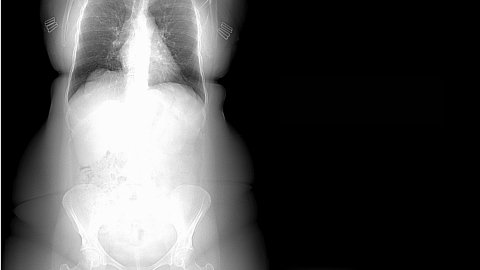

This experience is counter balanced by a CGI journey inside Victoria’s body. Working with 3D artists, Victoria has bought to life the medical imaging she’s collected through out treatment. Cancer cells, CT scans, mammograms and ultrasound provide a 3D portrait of her body from the inside, out. Victoria makes visible the often invisible parts of cancer treatment, the sickness, the fatigue, the tears and the hair loss. The soundscape is the driving force at the heart of the VR experience as it captures Victoria’s inner monologue and memories of her year of treatment throughout the piece.

Finding the right CGI team was also essential, especially given it was the first time that Victoria had integrated spatial storytelling into her work. Victoria worked closely with executive producers, Darren Emerson from East City Films and Catherine Allen and Producer Shehani Fernando who has a wealth of non fiction VR experience from her time at the in-house VR studio at The Guardian. Victoria also collaborated with Creative technologist Luca Biada. “I had access to all my medical records from King’s Hospital, so all the images in the VR experience are taken from my body. The cancer cells are mine and because I had staging investigations, we were able to work with my CT scan. Using Unity Luca put these images through volumetric capture to explore the CT scan in 3D. I was so lucky to work with amazing technologists throughout the experience.”